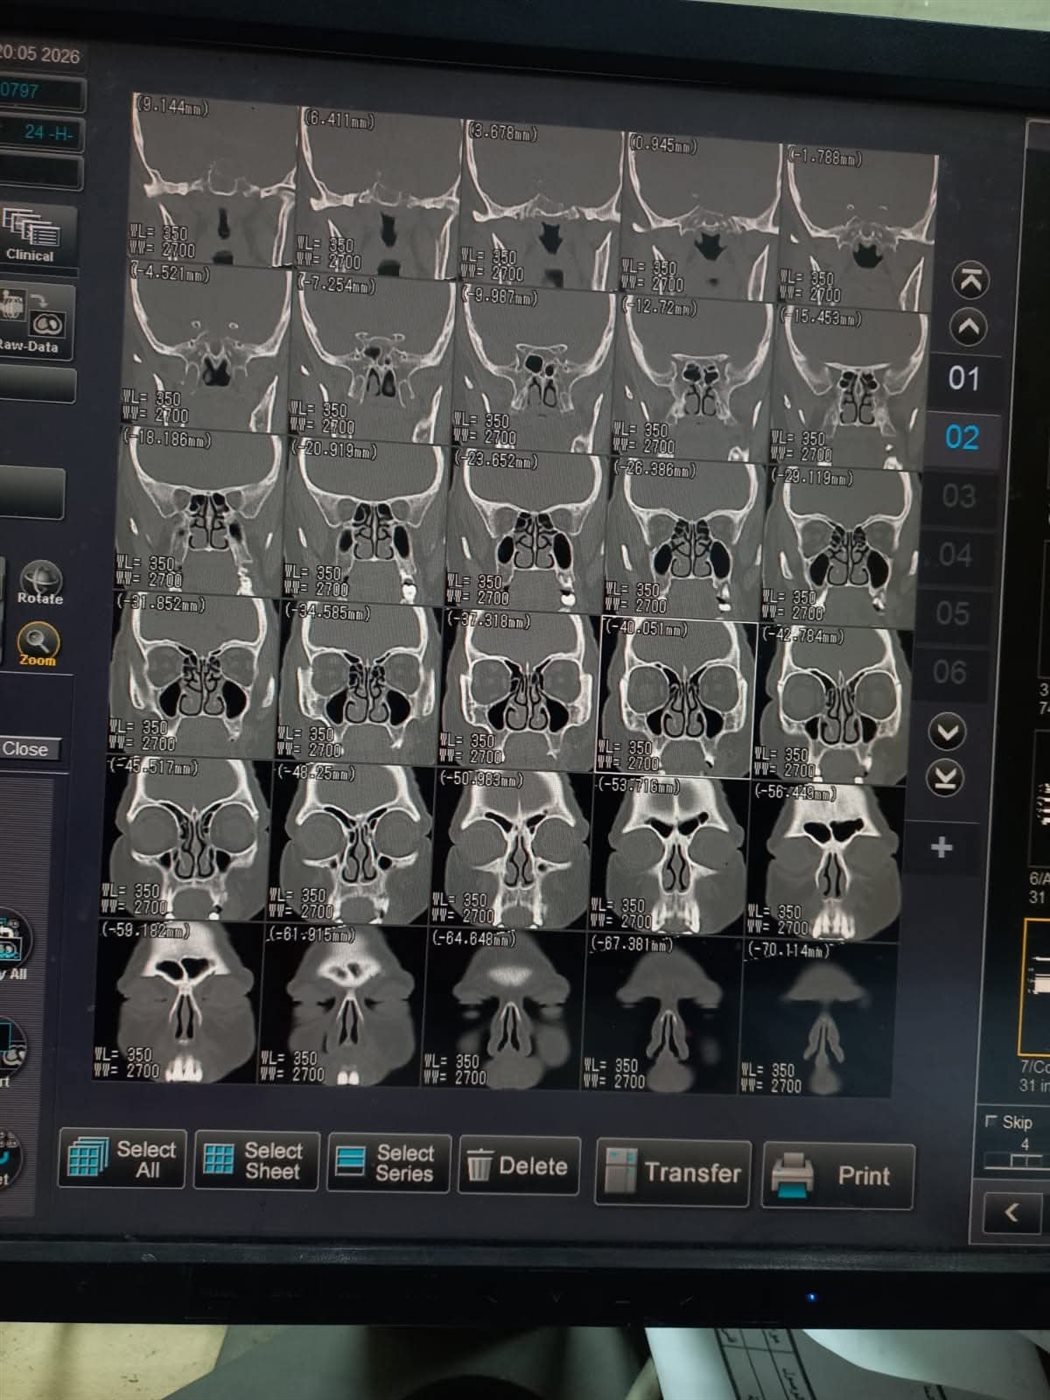

نجح فريق طبي مشترك من قسمي جراحة الأنف والأذن والحنجرة وجراحة المخ والأعصاب بمستشفى بني سويف الجامعي، في إجراء جراحة دقيقة لاستئصال ورم بالغدة النخامية لسيدة في العقد الخامس من العمر، باستخدام المنظار الأنفي الضوئي دون الحاجة إلى إجراء جراحة خارجية.